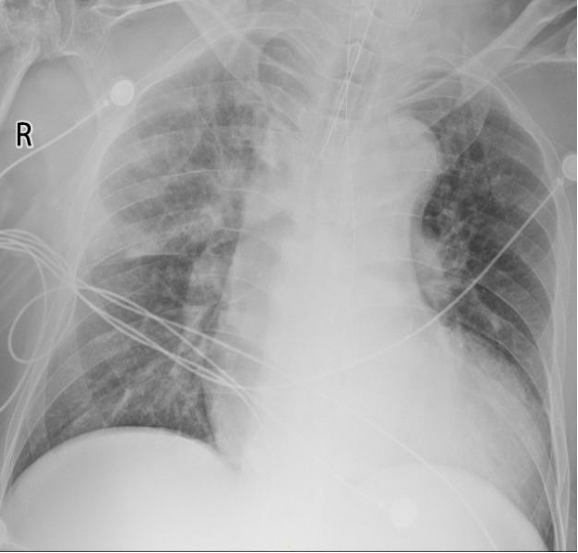

5月3日胸片:双肺渗出(图7)

7  患者胸片(2025-05-03)